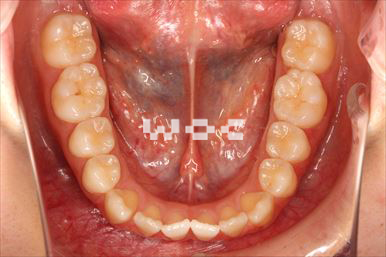

出っ歯エッジワイズ装置

特に装置の希望はなかったので、エッジワイズ装置を選択。

歯の移動量が大きいので歯根吸収の可能性がありましたが、目立った吸収は見られませんでした。-

- 年齢:17歳女性

- 主訴:出っ歯、前歯のガタガタが気になる

- 基本矯正料金:78万円

- 治療期間:1年2ヶ月

- 抜歯部位:上顎両側第一小臼歯